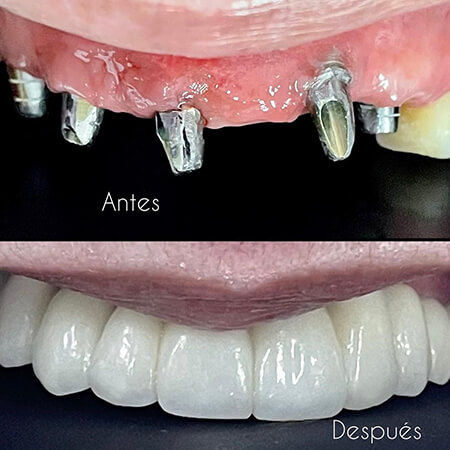

Before and After Gallery

The specialties of CFC Carlos Fernández De Castro are: Cosmetic dentistry, Dental implant, Oral rehabilitation, Periodontics, General dentistry, Pediatric dentistry, Orthodontics, Oral and maxillofacial surgery, Endodontics, Dental radiology, Prosthodontics, Maxillary orthopedics.

Excelente clínica odontológica. Me realice 2 implantes dentales y un diseño de sonrisa y quede muy satisfecho con los resultados. Recomendado el Dr. Carlos Fernandez de Castro y su maravilloso equipo.